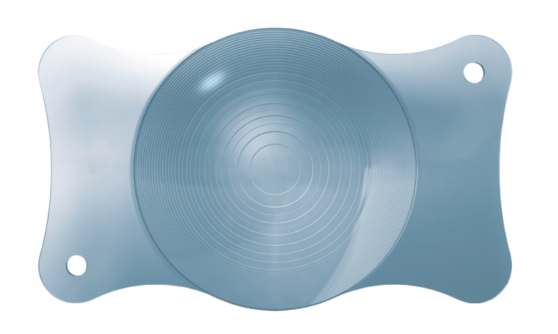

Die Optik der bei EuroEyes eingesetzten Multifokallinsen wird mit Hilfe der patentierten SMP-Technologie gefertigt: durch ein spezielles Verfahren werden Streulichtphänomene, die bei Multifokallinsen immer auftreten, auf ein absolutes Minimum reduziert. Der positive Effekt: weniger Blendung und weniger Halos (Lichtkränze). Darüber hinaus sorgt die asphärische Optik für eine optimierte Bildqualität und ein verbessertes Kontrastsehen unter reduzierten Lichtverhältnissen wie bei Dämmerung oder in der Nacht.

Die Optik der bei EuroEyes eingesetzten Multifokallinsen wird mit Hilfe der patentierten SMP-Technologie gefertigt: durch ein spezielles Verfahren werden Streulichtphänomene, die bei Multifokallinsen immer auftreten, auf ein absolutes Minimum reduziert. Der positive Effekt: weniger Blendung und weniger Halos (Lichtkränze). Darüber hinaus sorgt die asphärische Optik für eine optimierte Bildqualität und ein verbessertes Kontrastsehen unter reduzierten Lichtverhältnissen wie bei Dämmerung oder in der Nacht.